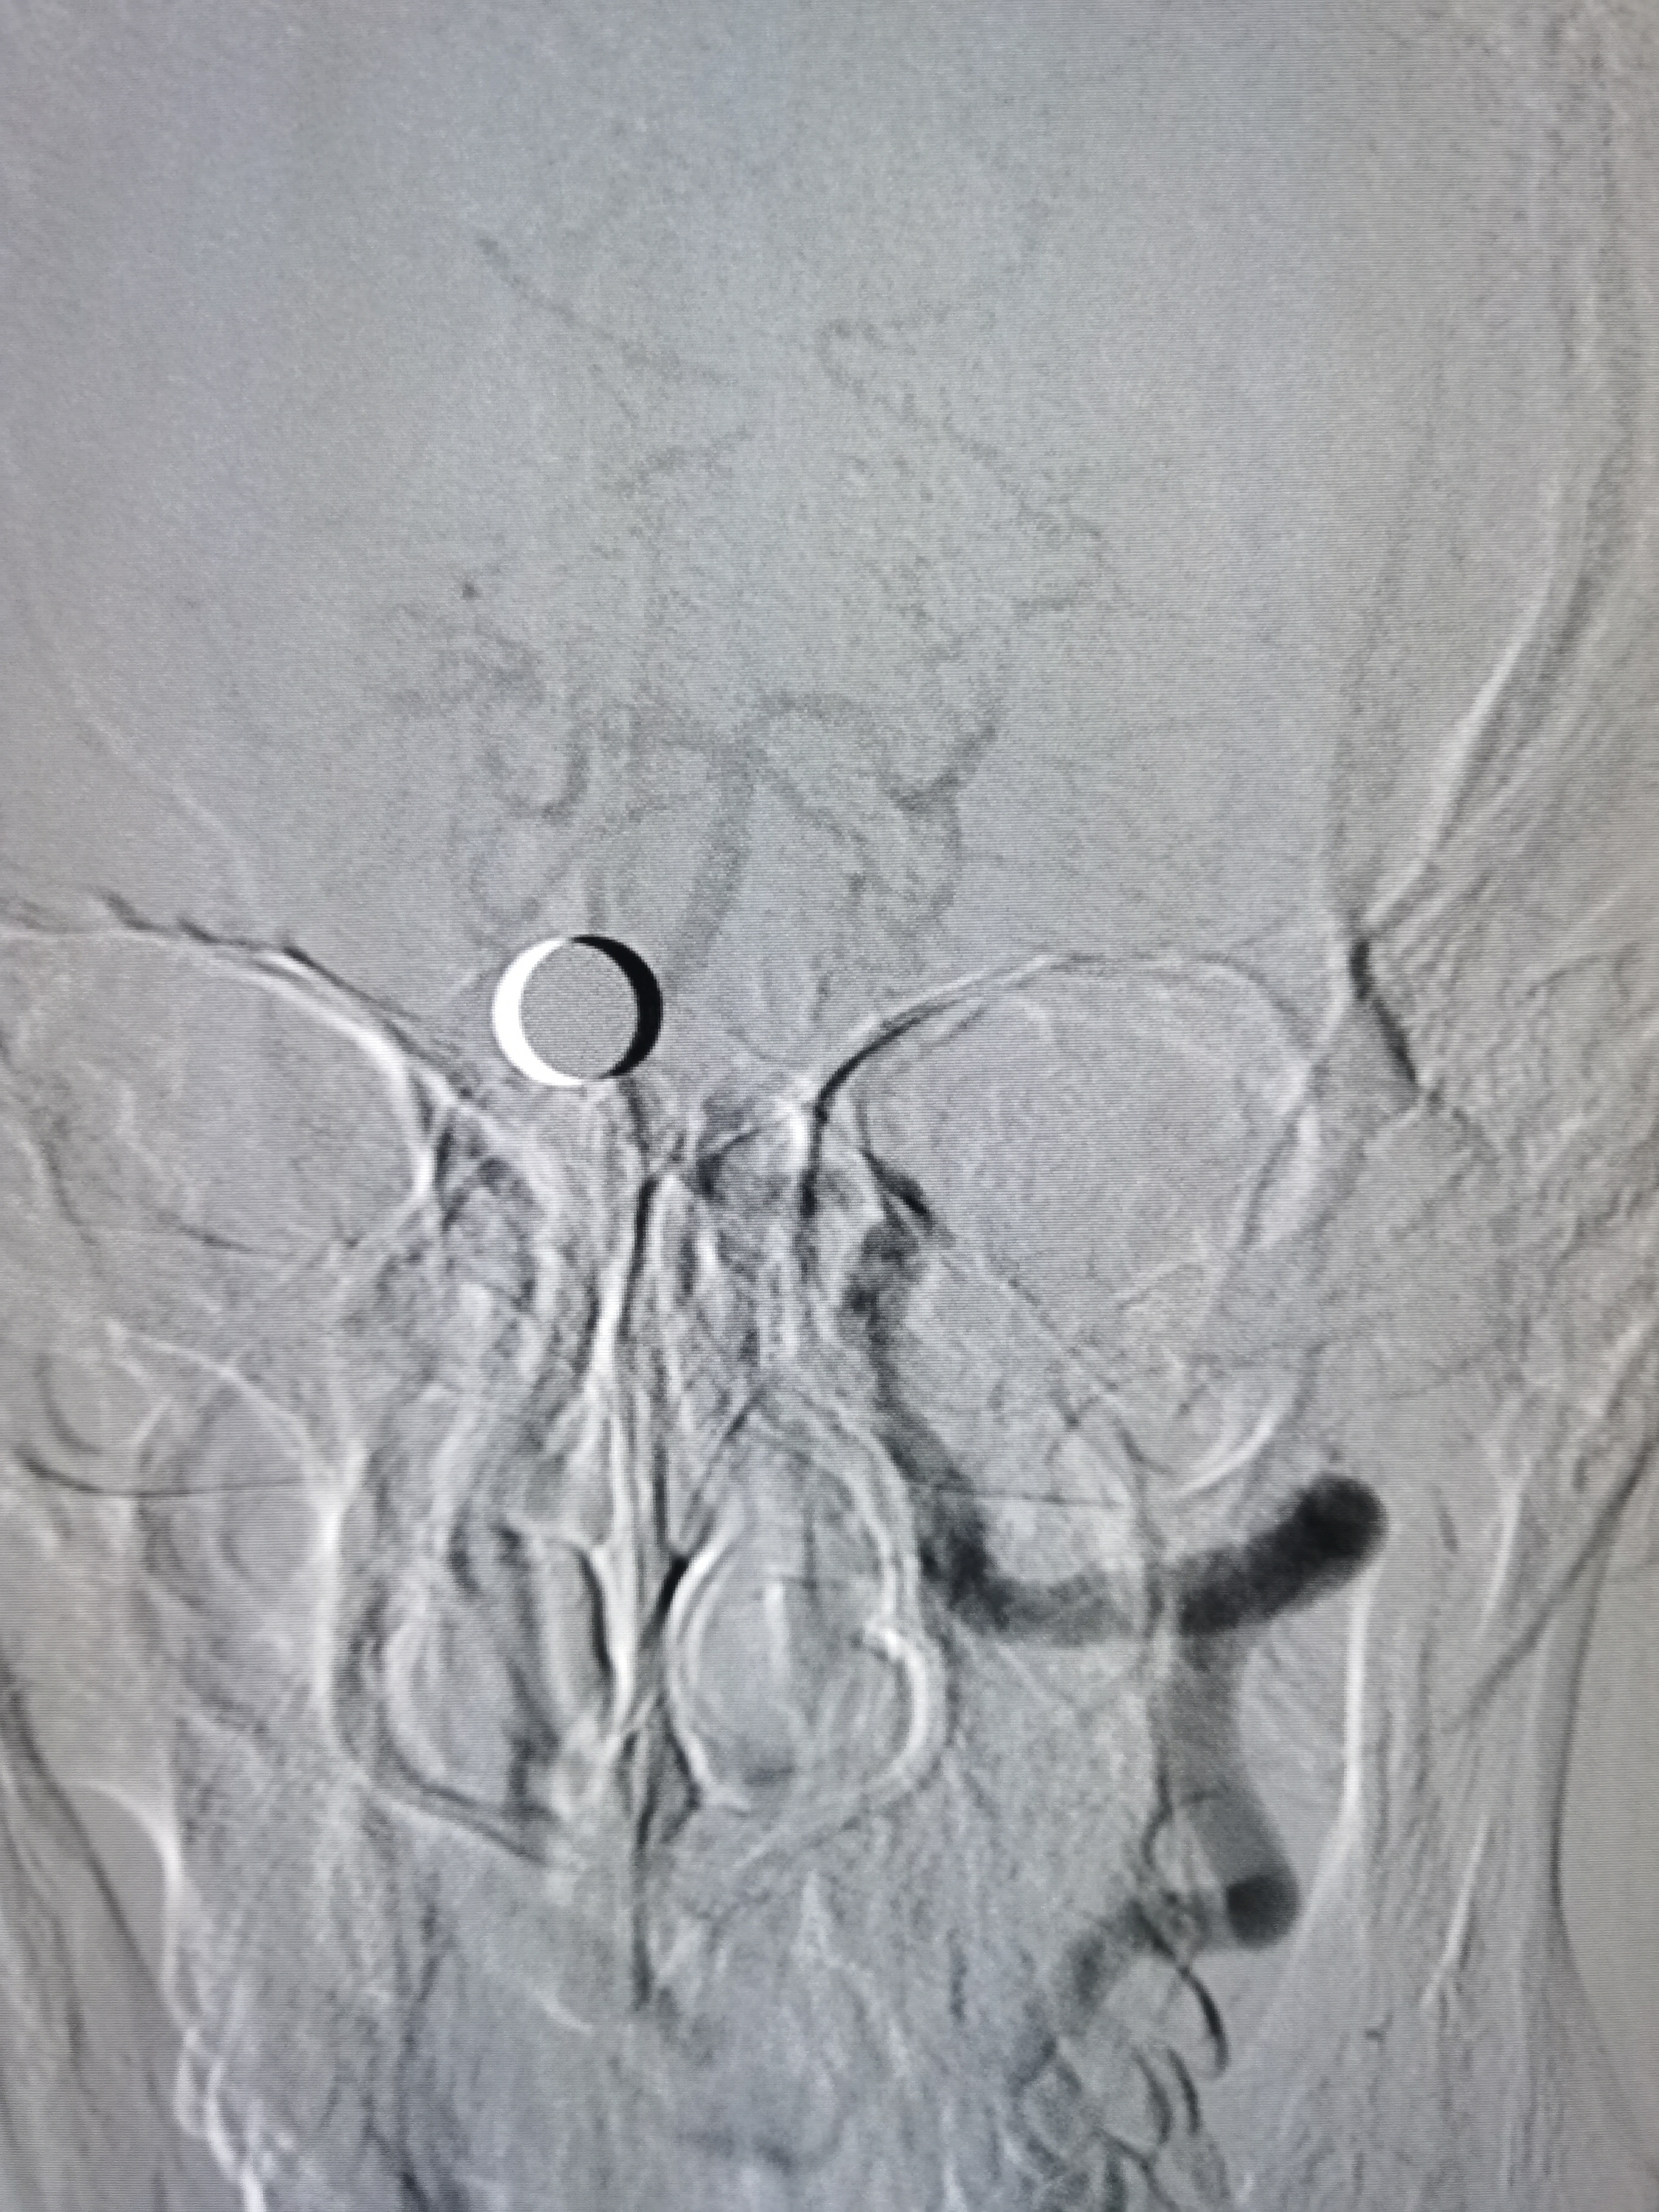

左侧颈内动脉起始部正常。

左侧大脑前动脉发育不良。

左侧大脑中动脉显影正常。

右椎动脉劣势。

颅内血流可。

左椎动脉优势。

基底动脉显影正常。